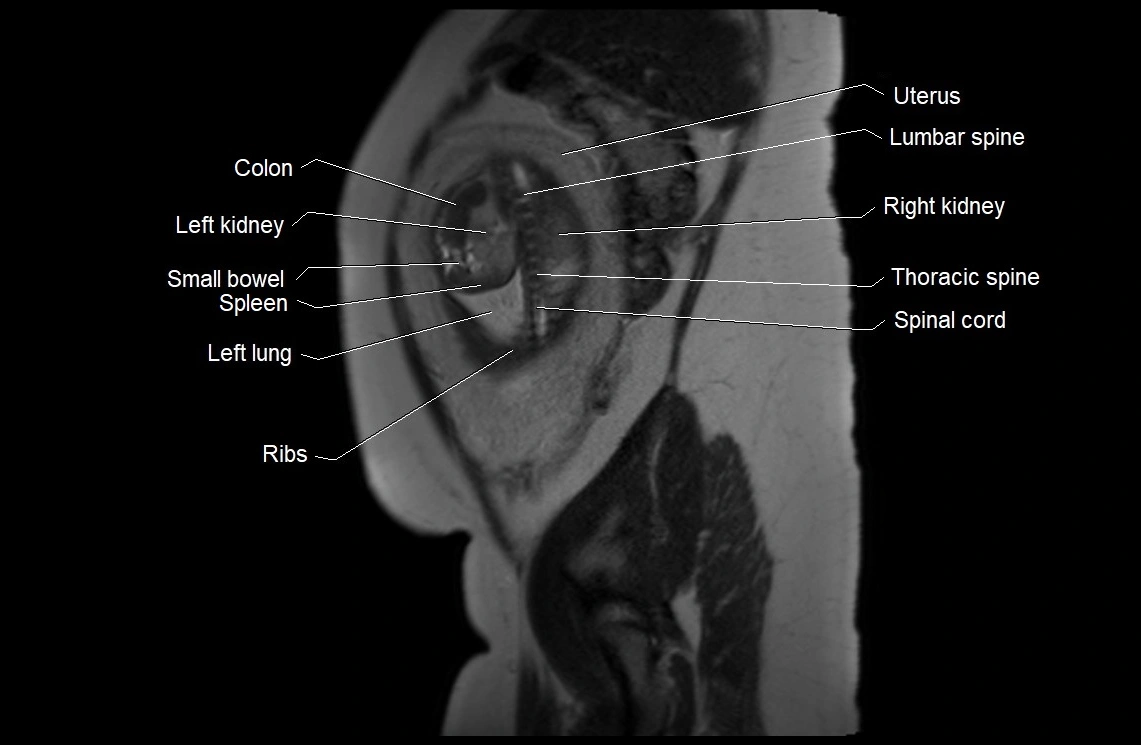

MRI Appearance

T2 HASTE (T2 GRE):

• Amniotic fluid shows very bright hyperintense signal

• Provides natural contrast against fetus and placenta

MRI image

image